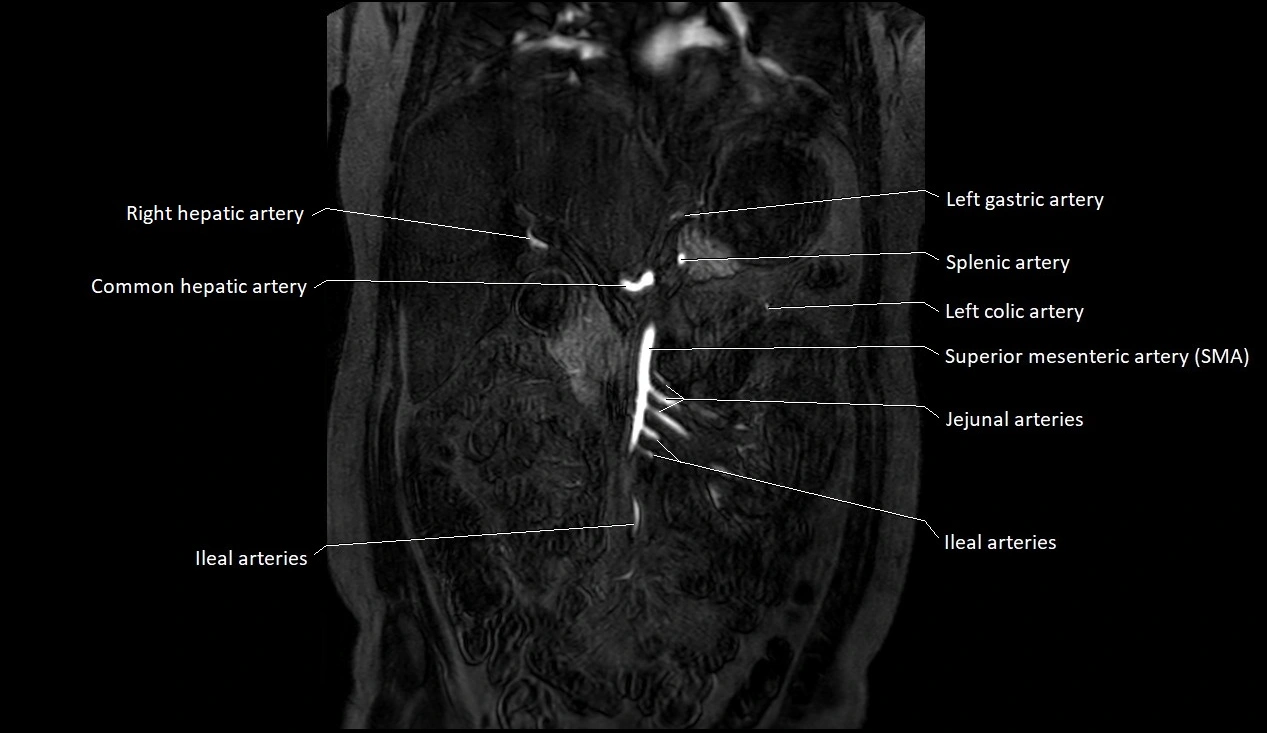

MRI images

image